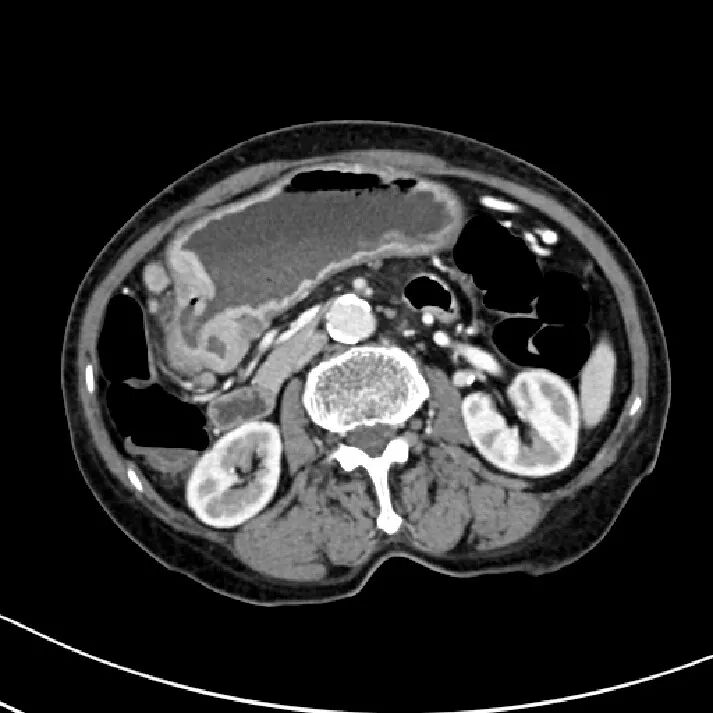

胰腺损伤

在交通意外中,尤其是汽车驾驶人员当汽车高速行驶中,汽车骤然撞于物体上,其强大的惯性使驾驶者的上腹部撞击于汽车方向盘上,导致胰腺受伤。有时当人体自高处坠落,腰部呈过度层曲,同时双侧肋弓极度内收,瞬间一个暴发力,挤压于胰腺上,造成胰腺不同程度的损伤。

胰腺损伤的部位,随外力的方向而异,以胰腺头、体部常见。当外力作用于右上腹或脊柱右侧方,则胰头部易被挤压,同时常合并有十二指肠、胆道、肝脏损伤,此类损伤后果严重,死亡率甚高可达70%~80%;当外力直接作用于上腹中部,则损伤多为胰颈、体部的部分或完全断裂,并合并有肠系膜上动脉损伤;外力作用于脊柱左侧方,胰尾常易受伤,此时多伴有脾破裂。